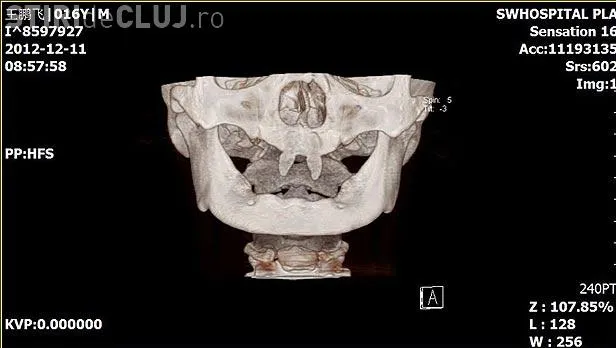

Un băiat din China i-a uimit pe medici, după ce i-au crescut doi canini foarte ascuţiţi, neavând alţi dinţi în gură.

Wang Hui, mama lui Wang Pengfei, și-a dus băiatul la un spital local din Chongqing (sud-vestul Chinei), pentru a vedea ce se întâmplă.